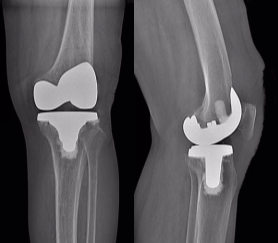

术前准备完善后,北京大学第三医院关节外科专家李杨副主任医师来到延安为两位患者先后实施了左侧人工全膝关节表面置换术。术中见膝关节软骨磨损严重,克服了因下肢力线与畸形、骨质缺损、骨骼质量、肌肉萎缩、关节强直等引起的种植体的准确放置、韧带间的平衡和肢体对线的恢复等诸多难题,为他们顺利植入了仿生的人工假体。

全膝关节置换术是治疗终末期膝骨关节炎的一种有效且持久的治疗手段,通过将膝关节中的受损部分切除,使用仿真人工关节替代的手术方式,随着对膝关节生物力学研究的不断深入,膝关节假体设计理念不断更新,人工膝关节置换手术也日趋成熟。对于终末期骨性关节炎特别是伴有畸形的患者来说,全膝关节置换术是一种行之可靠的治疗手段。只要适应症选择正确,假体选择恰当,术中精细操作,术后早期积极主动功能锻炼,不仅能减轻患者的疼痛,重建关节功能,更能提高老年患者的生活质量。